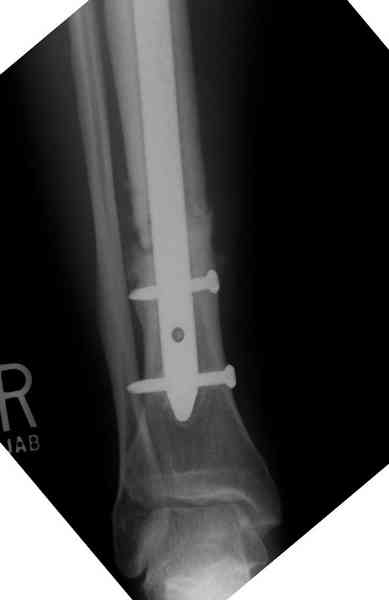

Недавно на нашей ежемесячной Morbidity&Mortality

conference мы разбирали похожий случай, ложный сустав большеберцовой кости после резекции опухоли.

К нашему онкологу-ортопеду обратился больной с жалобами на боли в голени, из рассказа - год назад была сделана биопсия большеберцовой кости, но название заболевания "не запомнил”.

Оперирован в военном госпитале с заменой сегмента

аллокостью большеберцовой кости и после демобилизации явился для постоянного наблюдения по месту жительства.

Наши имели проблему со сращением, пришлось им сделать динамизацию, дополнительную аутопластику.

Снимки представлены.